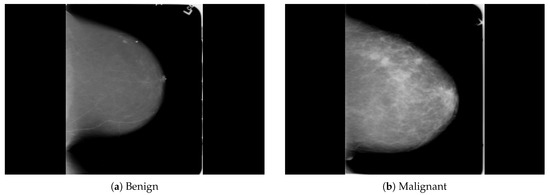

Figure 2. An example of breast mammogram images from the PINUM dataset. (a) The benign image. (b) The malignant image. The images were labeled by the expert radiologist in the dataset.

The dataset was collected from a local (PINUM) hospital [51] in Pakistan, with the approval of the Diagnostic Imaging Nuclear Medicine and Radiology Research and Development Committee. A total of 289 patients were manually labeled by the expert radiologist using the initial mammogram reports generated by the mammography machine and included ages between 32 and 73 with a mean age of 48.5 years. The radiologist team consisted of two members, one being a senior radiologist and physicist holding a PhD degree in nuclear medicine with 10 years of experience and the second being a junior radiologist with a Master’s degree in radiology. The dataset was first evaluated with the proposed method to increase the sensitivity of breast cancer prediction using a fully automated CAD system. The dataset included 577 original images consisting of 425 benign and 152 malignant images with both MLO (mediolateral-oblique) and CC (craniocaudal) views at a resolution of 4096 × 2047, as shown in Figure 2. Each CC and MLO view image had a focal length of 35 mm with a 96 dpi resolution along the horizontal and vertical axis. The mammography exam of the PINUM dataset was acquired with Hologic 2D, 3D mammography. Data augmentation techniques were employed on the PINUM dataset to increase the size to regularize and train the deep convolutional neural network. Each mammogram image was rotated at four angles, obtaining five images, including one original and four rotated images. Moreover, we included another public dataset, the Digital Database for Screening Mammography (DDSM) [52], for the evaluation of our model, which contains 3568 mammogram images (1740 benign, 1828 malignant) from 870 benign and 914 malignant cases, as shown in Figure 3. We split the dataset into 60:20:20, where we used 60% for the training of our model, 20% for cross-validation, and the rest for testing. We used 5-fold cross-validation to test our dataset. A detailed description of the dataset is given in Table 1.